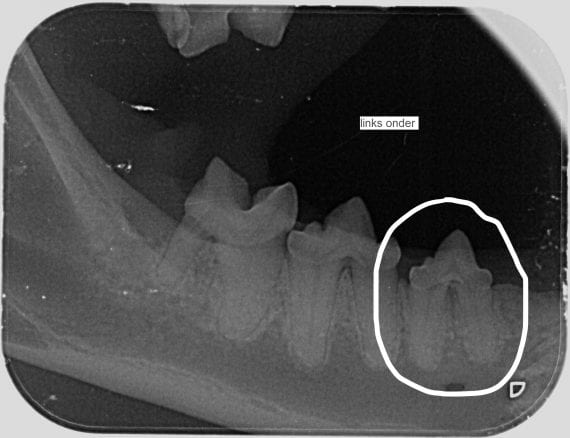

Onderaan deze pagina staan 2 dentale röntgenfoto's. Op de eerste foto hieronder zie je een kies die al bijna helemaal opgelost is. De foto ernaast laat een kies zien waarbij de wortels nog aanwezig zijn.

Uw kat krijgt eerst narcose en pijnstilling. Daarna maken we bij katten altijd dentale röntgenfoto's! De eerder genoemde resorptie letsels komen soms alleen voor in de wortels en zien we dus alleen met een röntgenfoto. Soms is de wortel zelfs al zo opgelost dat alleen de kroon van de tand verwijderd moet worden.